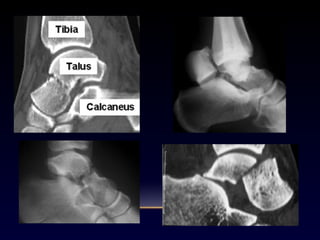

Talo

Articulación subtalar

Calcáneo

Articulación tibiotalar

Fractura

Fx pie

Fx calcaneo